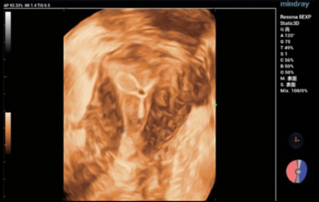

Female pelvic floor anatomy, which developed since the early 20th century, has had a variety of theories, including integral theory, three levels of vaginal support theory, "hammock hypothesis", and three-chamber system. Supporting structures such as pelvic floor muscles, fascia and ligament play an important role in maintaining the normal function of pelvic floor, among which levator ani muscle group is one of the most important supporting structures.